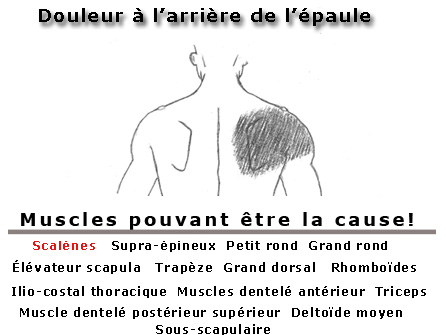

- Douleur à l'épaule

- Douleurs aux épaules